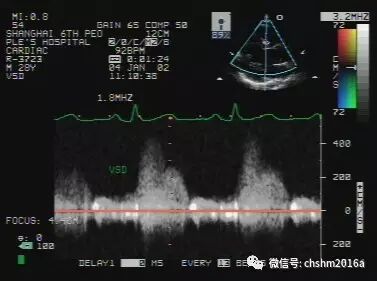

2.多普勒超声心动图

在室间隔回声连续中断处,可显示收缩期由左室向右室分流的高速正向湍流频谱,流速大小与肺动脉压力有关,严重肺动脉高压时,峰值流速大于3.5米/秒。

彩超伪像是什么先天性心脏病超声诊断(超声梦影像医生集团 CCM)_https://www.jmylbn.com_新闻资讯_第8张

图2.3.6   室间隔缺损连续多普勒频谱